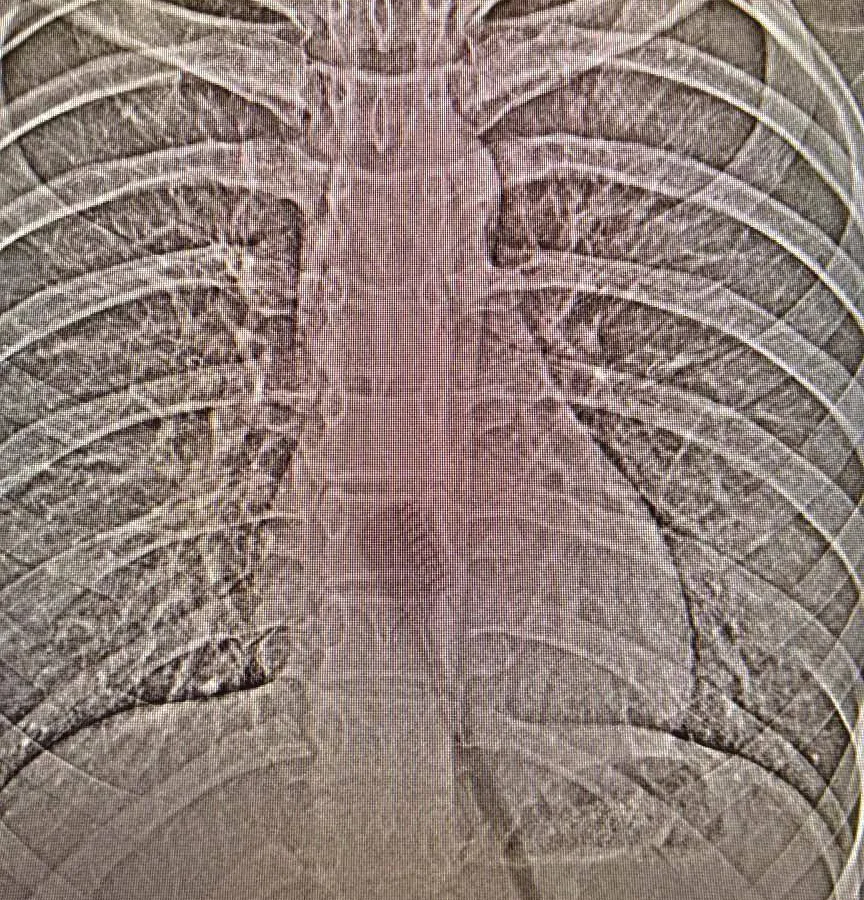

В Камском детском медицинском центре (КДМЦ) Челнов спасли 13‑летнюю девочку, которая случайно проглотила зубную щётку во время гигиенических процедур. Длина инородного предмета составила 19 см — он застрял в желудке и частично в пищеводе, создавая реальную угрозу здоровью. Об этом сообщает пресс-служба учреждения.

Благодаря оперативным действиям врачей ситуация разрешилась без тяжёлых последствий. Специалисты провели малотравматичную эндоскопическую операцию: щётку удалось извлечь без разрезов, максимально бережно. Пациентка быстро пошла на поправку и уже вернулась домой.